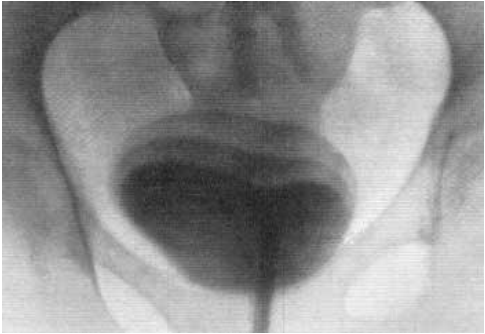

Медицинские изображения и примеры эксреторной цистографии